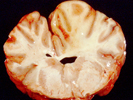

F. verticillioides e fumonisinas estão mundialmente distribuídos. As principais preocupações com a saúde associadas às fumonisinas são os efeitos agudos (exposição única), efeitos tóxicos em equinos e suínos e propriedades carcinogênicas (capaz de causar câncer (cancro, pt)). Cavalos envenenados com fumonisinas podem desenvolver uma doença fatal em conhecida como leucoencefalomalácia equina. Sintomas desta doença incluem sonolência, cegueira, desequilíbrio e liquefação do tecido cerebral (Figura 9). Os suínos envenenados com fumonisinas podem apresentar redução na ingestão de ração e no ganho de peso, danos no fígado e desenvolver uma doença fatal conhecida como edema pulmonar, na qual os pulmões dos animais são preenchidos com fluido. Em animais de laboratório as fumonisinas mostraram-se carcinogênicas e, em humanos, o consumo de milho contaminado com fumonisinas está associado com altas taxas de câncer (cancro, pt) de esôfago e defeitos no cordão umbilical. As fumonisinas foram caracterizadas pela primeira vez no final de 1980, como resultado de estudos sobre as causas de câncer (cancro, pt) de esôfago na África, juntamente com surtos de leucoencefalomalácia equina e edema pulmonar em suínos nos EUA.